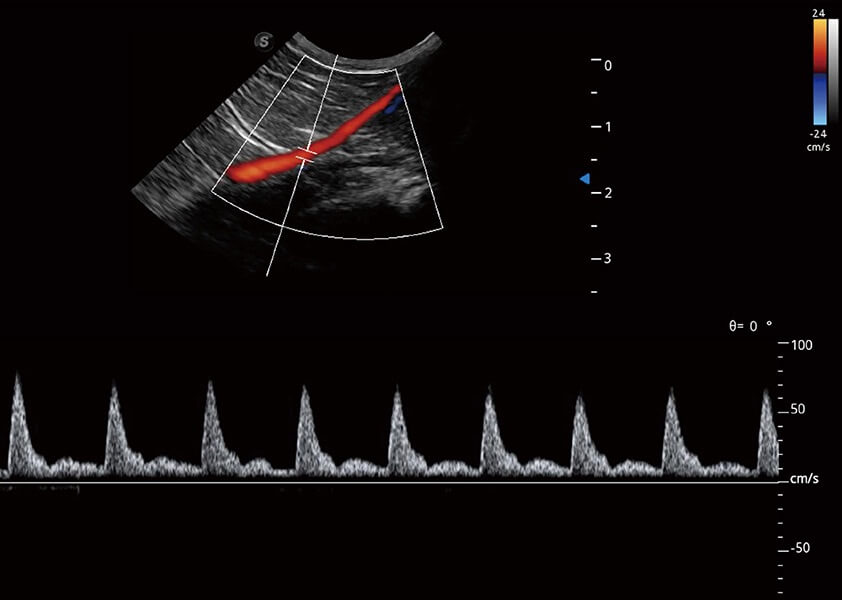

ProPet 60 作为一款高端台式动物超声设备,为动物医生的日常诊断提供了一系列贴合动物临床需求、解决临床实际问题的高级成像功能。凭借全系列高清探头,满足医生对腹部、心脏、生殖、浅表、肌骨等成像的所有需求,切实帮助您提升检查效率,提高诊断信心。

动物是人类最亲密的朋友和最值得信赖的伙伴。1xBET也一直致力于探索动物专用的超声影像解决方案。 全新推出的ProPet系列,是1xBET在动物超声影像智能化、专业化、精准化的一次跨越式革新。动物不能用言语来表述自己的不适,通过超声影像,ProPet系列搭建了动物医生与不同物种沟通的“桥梁”,为动物医生注入了“治愈之力”。